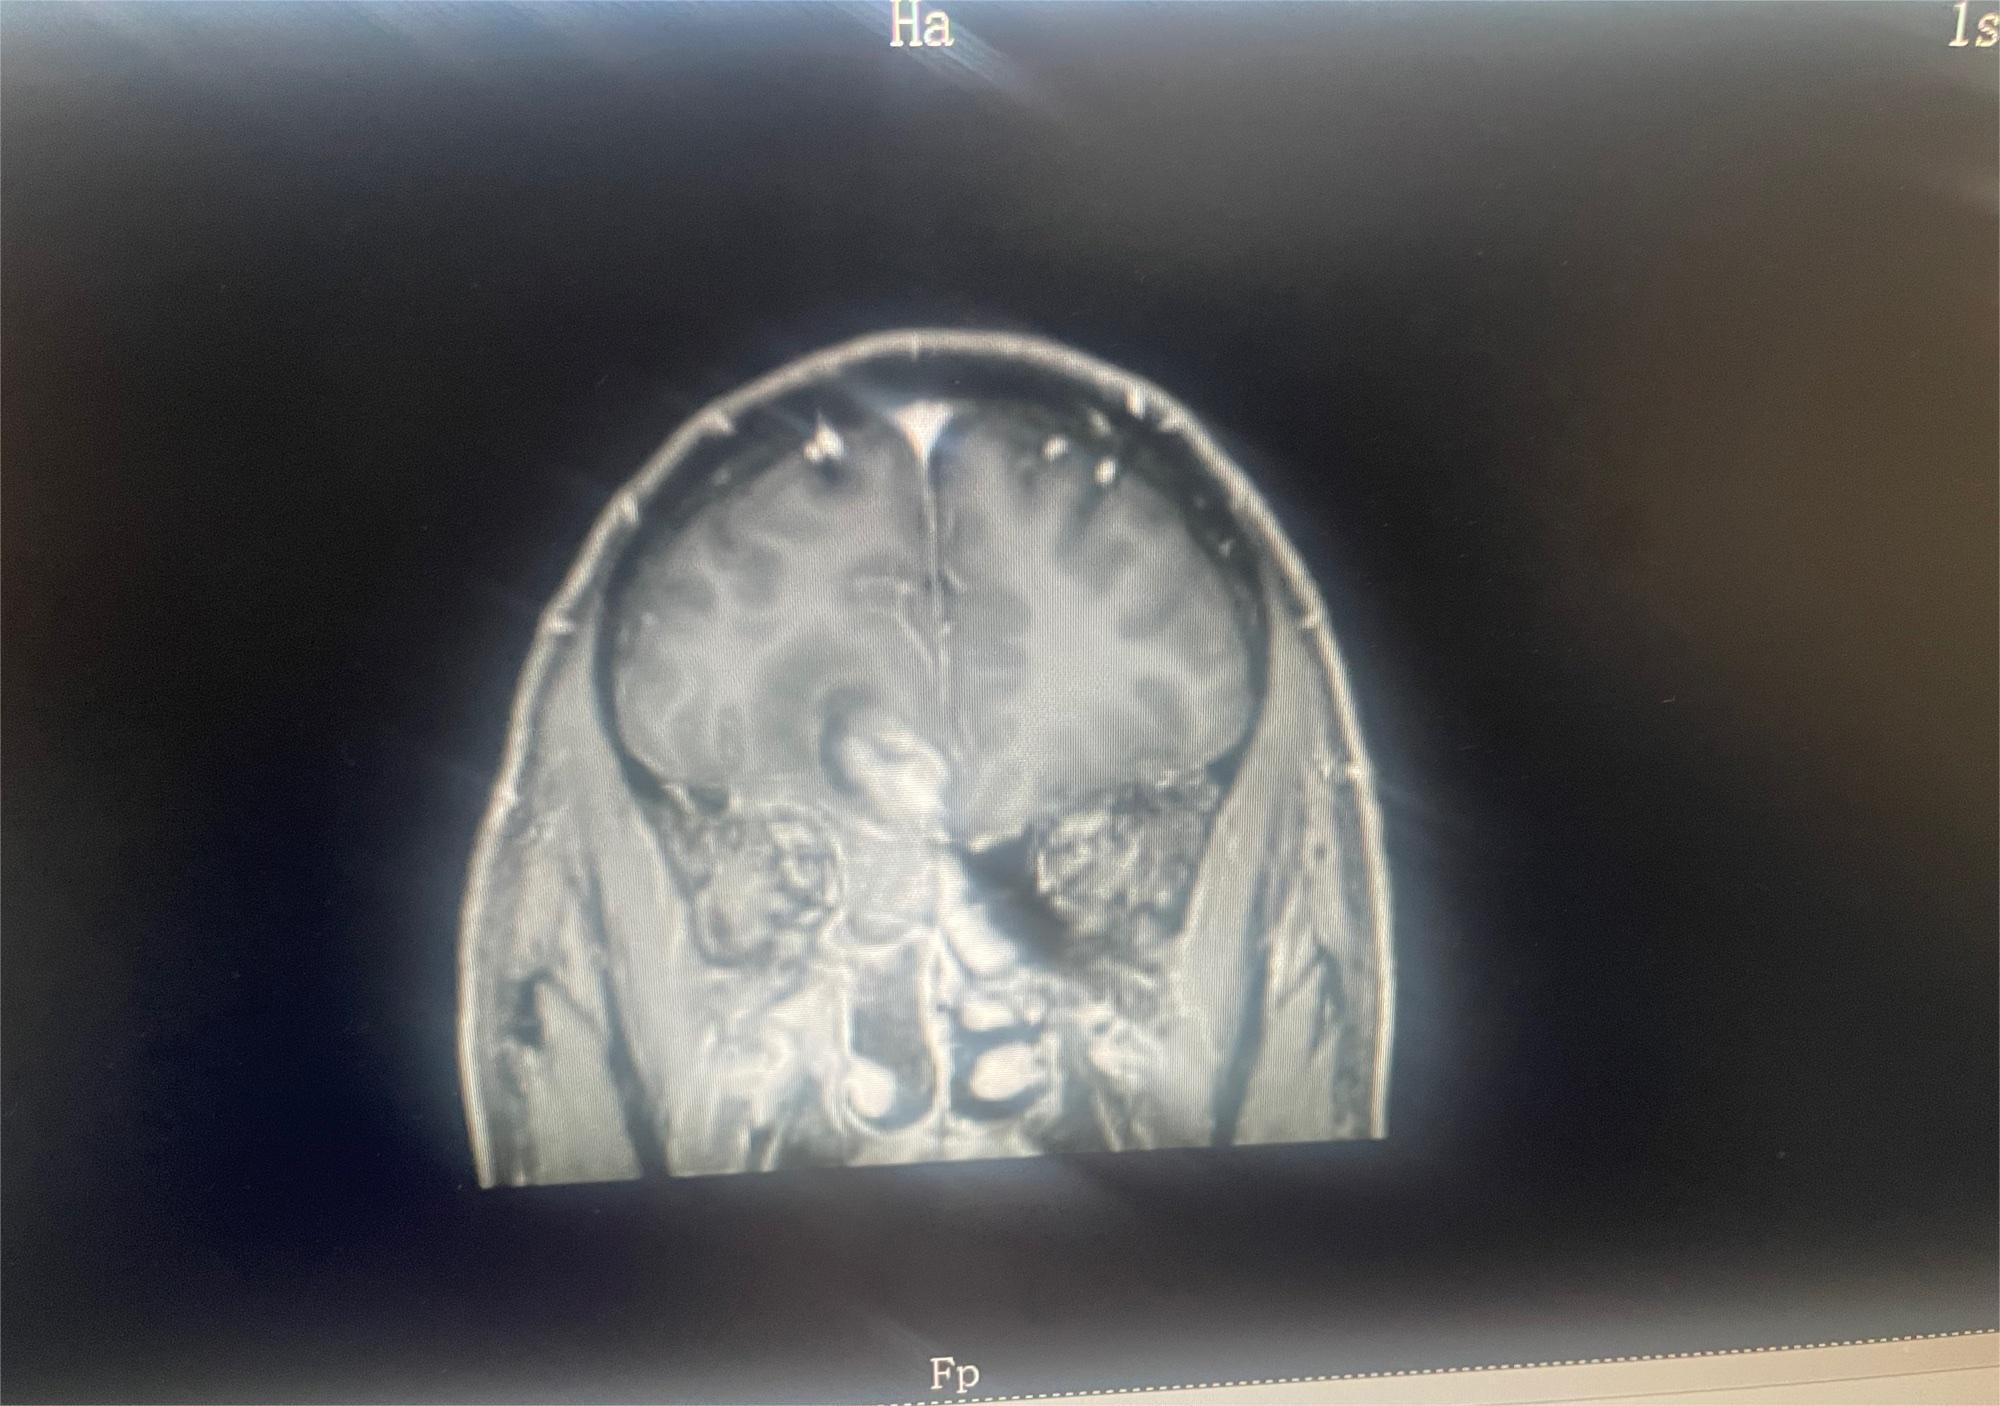

键盘侠666  0

2024-03-21   患者家属

求助有没有比较好医院或者治疗好的方案

共1张

脑部肿瘤求助